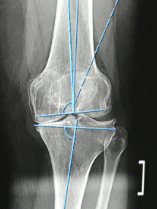

After several years of cortisone and Synvisc shots, I finally went locally to two surgeons to discuss a full knee replacement. In these visits I was turned away, which made me feel very discouraged. I then reached out to our corporate medical doctor who suggested that I see the best orthopedic doctor in the country and that is when I found Dr. Danyal Nawabi! My very fist consultation with him I knew I was in the right place. He was very optimistic and ensured me he could fix this ongoing problem that was affecting my quality of life. He explained in detail why I was in so much pain and told he me that he could fix it! I never thought I would hear those words after being turned down previously. I immediately scheduled my full knee replacement surgery which took place 3 months after my first consultation. The surgery went well and I woke up feeling relieved of all pain. I am now 6 months post operation and feel like a new woman! Every visit with Dr. Nawabi he ensures me that I made the right decision and he extended my life. I am forever grateful. Thank you Dr. Danyal Nawabi!